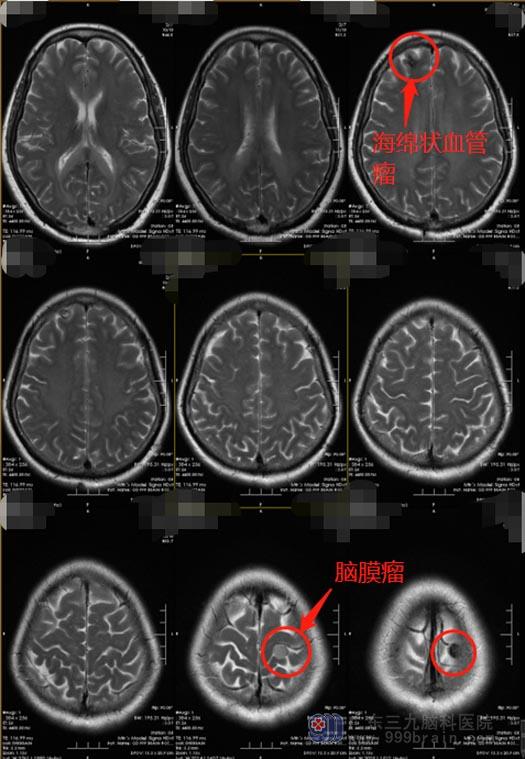

55岁的林阿姨在半个多月前突然感觉到脖颈和颜面部大汗淋漓,以为是更年期的常见症状。家人陪她去医院检查内分泌,头颅MR检查意外发现“1.左侧额顶部中央区颅骨内下小脑膜瘤;2.右侧额叶皮层异常信号,考虑海绵状血管瘤”。

按照传统疗法,患者需要接受二次单独的开颅手术,才能逐一切除肿瘤。医院副院长、神经外五科主任鲁明带领团队在详细检查的基础上,精心制订手术方案,决定用一次手术机会同时切除颅内二处不同部位的不同病灶。家属知情同意后,由鲁明主刀在全麻下行“右额叶海绵状血管瘤及左顶部脑膜瘤切除术”,术中导航精准定位病灶范围,显微镜下将二个肿瘤顺利全切。